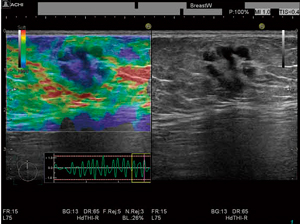

カラー化当初は,腫瘍部(硬い部分)を赤に,正常部を青にしましたが,逆にして,腫瘍部を青にしたところ,後ろ側のBモードがよく透けて見え,診断しやすくなりました。カラー化することで,質的診断ができるというエラストグラフィの最大のメリットを生かすことになります。

エラストグラフィは,圧を加えた時の組織の変化を画像化しますが,経験を重ねるうちに,圧を加える操作,つまり,プローブで押す速さは個人差が大きいことがわかってきました。加圧時のフェーズの計測では,この個人差が画像に与える影響は小さくありません。一方,変形した組織が自然に元に戻る時は,組織固有の変化となるため差が少ないことから,組織が戻るフェーズの弾性率を計測することを思いつきました。そこで,圧迫の状況を可視化するため,組織の歪みの時間変化を波形表示するStrain Graph機能を開発し,リアルタイムに圧迫の速さや周期を確認しながら,安定したフェーズで計測するようにしました。また,さらに安定したデータを得るために,Strain Graphを解析して,フレームを自動で選択する機能も開発しました。これは,平均化に有用であると考えています。